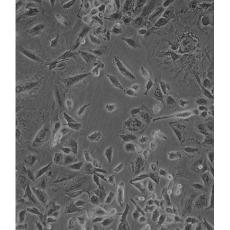

NCI-H1975

中文名稱 人肺腺癌細胞

組織來源 肺腺癌;女性

生長特性 adherent

形態特征 epithelial

細胞描述 該細胞是1988年7月從一名女性(無抽煙史)非小細胞肺腺癌組織中分離得到的。